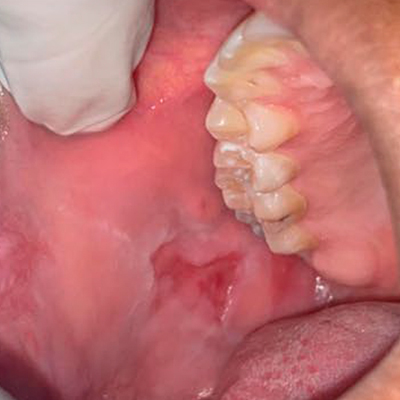

Dor, inchaço, ou sensação de que algo

está errado na boca, gengiva ou língua?

Fonte: Lopes DN et al. Co-occurrence of oral pemphigus vulgaris and herpes simplex virus in a young patient with Crohn’s disease. BMC Oral Health. 2020.